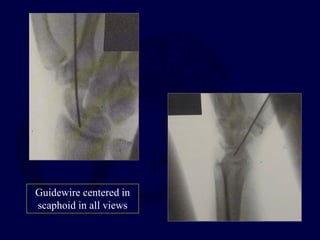

Percutaneous Fixation

Volar

Dorsal

Guidewire centered in

scaphoid in all views

Derotation pin

cannulated drill

Cannulated Screw